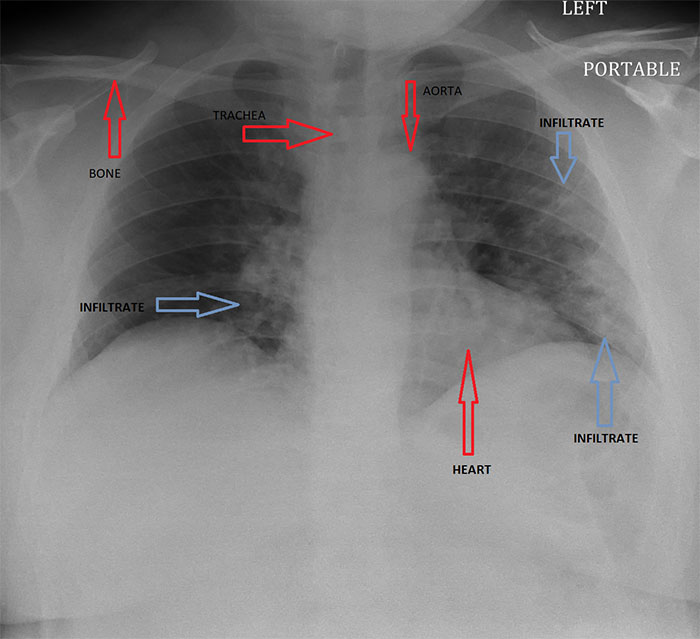

Imgur user and radiologist HeyYoMikey8 said the unknown future is the hardest part of the coronavirus pandemic. HeyYoMikey8 believes it is our own responsibility to educate ourselves so we can all do our part during these difficult times. So, to make it easier for us, the health professional shared what they’re seeing in cases of Covid-19 radiographically. The comprehensive commentary, as well as images used to help in the diagnosis and managing complications or evaluating the progression of the disease, should definitely broaden your understanding of what we’re all facing.

Interestingly, in the early days of the coronavirus outbreak, radiological imaging was not regarded as a way to confirm evidence for COVID-19 cases. Instead, authorities relied on a positive result of the PCR nucleic test. The supply of the PCR test kits, however, was limited and getting back the results took a long time. So, Chinese health authorities soon recognized these difficulties and changed the diagnostic strategy in their 5th edition of the Guidelines on Diagnosis and Treatment of COVID-19. As a result, radiological features of COVID-19 were included as one of the three determinant clinical manifestations to confirm a suspicious patient. The high efficiency, reliability, and accessibility of the radiological diagnostic technology have helped tremendously in identifying the disease. These processes were soon enhanced further by the introduction of artificial intelligence (AI) algorithms.

This could mean CT scanners were to be shut down for up to an hour after a single scan, severely limiting throughput for other patients including for emergent indications like trauma. “The radiology technologists are the real unsung heroes in all of this as they have to deal directly with many potentially infected patients to get their imaging done timely and appropriately, and should be seriously commended right now. We face problems with the diagnosis because a negative study does not rule out the disease, as it may have not yet manifest as an infiltrate despite the infection being present (false-negative scans).”

“Secondly, although certain concerning patterns suggesting COVID-19 on imaging have emerged, all findings are strictly nonspecific and therefore do not entirely rule in the diagnosis, and require additional confirmation as it could still be other entities such as Influenza pneumonia.”

“Finally, all radiology is a business like any other, and we have canceled or deferred almost all elective imaging procedures to help stall the spread of infection and make room for a potential surge of COVID-19 cases,” the radiologist explained. “Therefore, our imaging volumes have dropped by upwards of 50% basically overnight, leaving us with a lack of work for our normal staffing (requiring forced vacations) and a large dip in revenue which jeopardizes our ability to pay the bills and keep our nonphysician employees employed and paid. I do think radiology has helped us at least in this early stage to identify many presumptive cases that were not being considered as COVID-19 at their presentation … It may be helpful for follow up evaluation for potential complications such as ARDS or pleural effusions. Also, there are patients with respiratory symptoms now concerning COVID-19 that have imaging findings/patterns more consistent with other etiology such as bacterial pneumonia or pulmonary embolism, therefore helping to rule out many cases and guiding other appropriate treatment.”